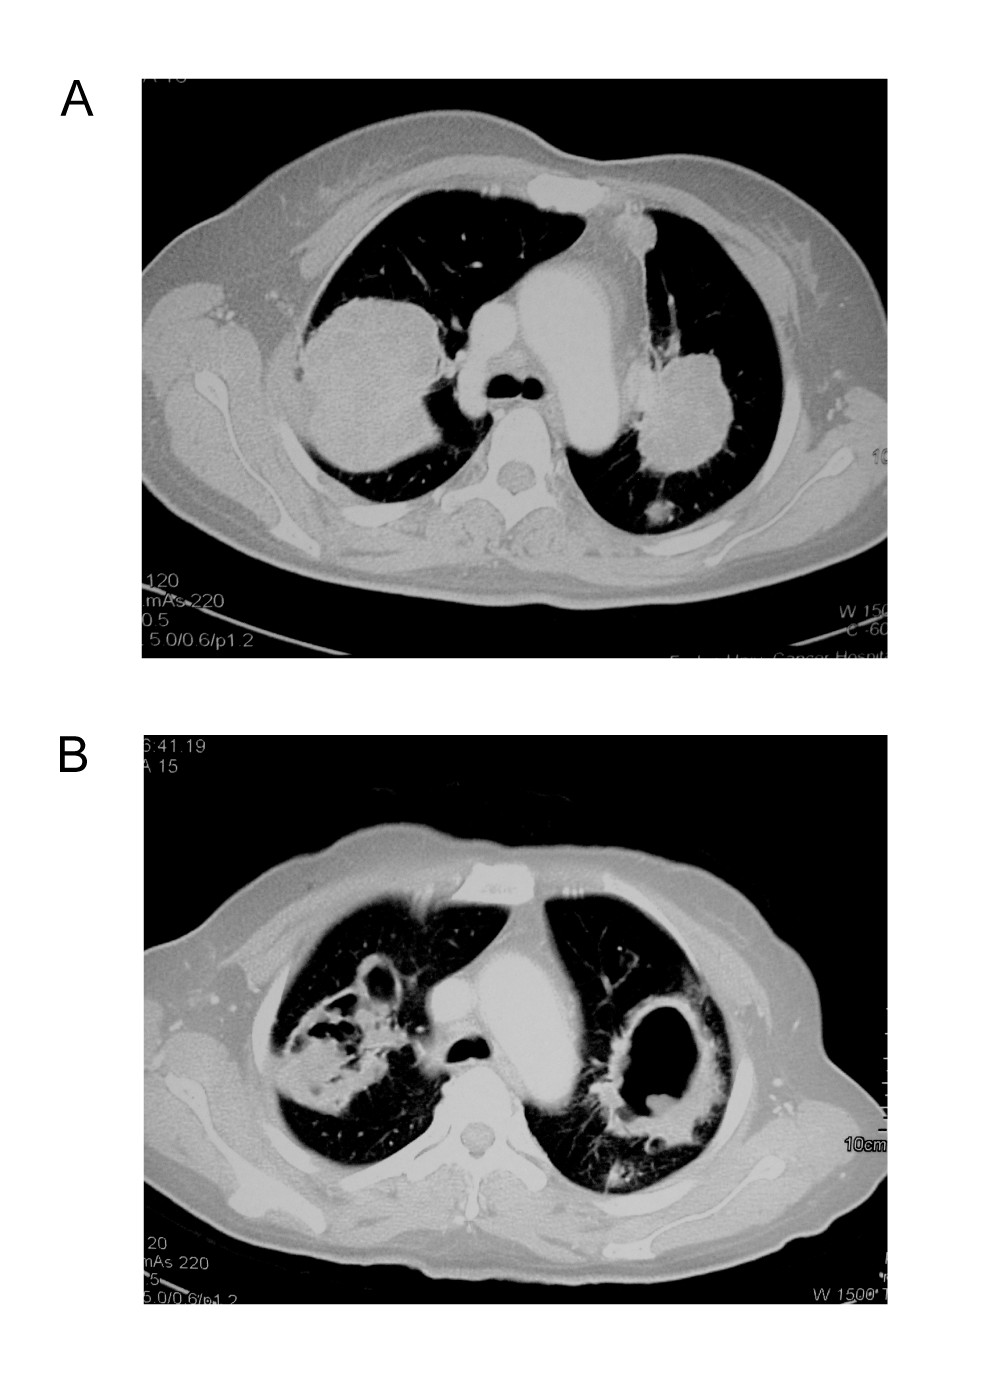

A 45-year-old female with metastatic rectal cancer involving the liver and lung, who had failed prior treatment of 2 cycles of FOLFOX4 regimen, 4 cycles of liver chemoembolization, and 4 cycles of FOLFIRI, treated at 750 mg qd dose level, had a partial response. Compared with the baseline CT-scan, the same lesions on day 53 showed cavity formation and decreased density. Further CT-scan confirmed partial response. Because of hand-foot syndrome, diarrhea and stomatosis, she received reduced dose of 500 mg qd until disease progression (on day 255). Figure 1

Figure 1

Computerized tomography scans of the metastatic tumors at baseline (A) and after 2 months (B) showing cavity formation.